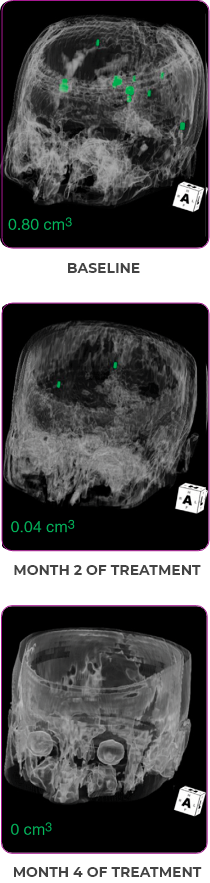

PATIENT CASE:

METASTATIC, RAIa-REFRACTORY,

PAPILLARY THYROID CANCER1

- 56-year-old female with PTCa that had metastasized to multiple sites, including the brain

- Progression after first- and second-line systemic treatment

- PRa after 4 weeks on VITRAKVI® (larotrectinib); CRa after 8 weeks

- At last assessment, complete response was sustained over an 11-month period

Response to VITRAKVI1

- After 8 weeks on VITRAKVI, all target lesions had disappeared, demonstrating a complete response

- The complete response was sustained over 11 months of treatment with VITRAKVI

- Patient experienced Grade 1 fatigue and mild hepatic enzyme elevation

Response in primary and metastatic lesions1

MRIa imagery of the lungs. Arrow indicates large target lesion in left lung.1

SCAN 1: LUNG

MRIa imagery of the brain. Arrow indicates large target lesion in left lung.1

aMRI, magnetic resonance imaging.

Images courtesy of Dr Fabian Pitoia.